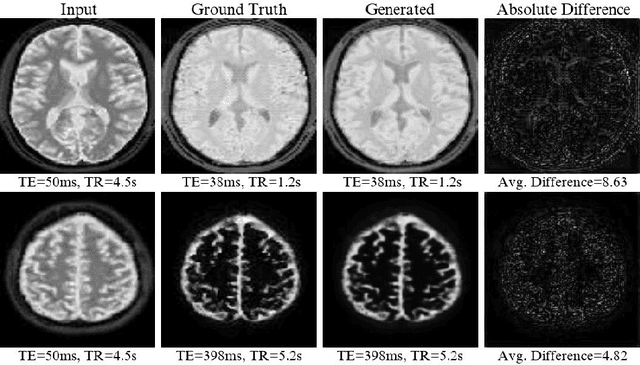

Abstract:Magnetic resonance (MR) image re-parameterization refers to the process of generating via simulations of an MR image with a new set of MRI scanning parameters. Different parameter values generate distinct contrast between different tissues, helping identify pathologic tissue. Typically, more than one scan is required for diagnosis; however, acquiring repeated scans can be costly, time-consuming, and difficult for patients. Thus, using MR image re-parameterization to predict and estimate the contrast in these imaging scans can be an effective alternative. In this work, we propose a novel deep learning (DL) based convolutional model for MRI re-parameterization. Based on our preliminary results, DL-based techniques hold the potential to learn the non-linearities that govern the re-parameterization.